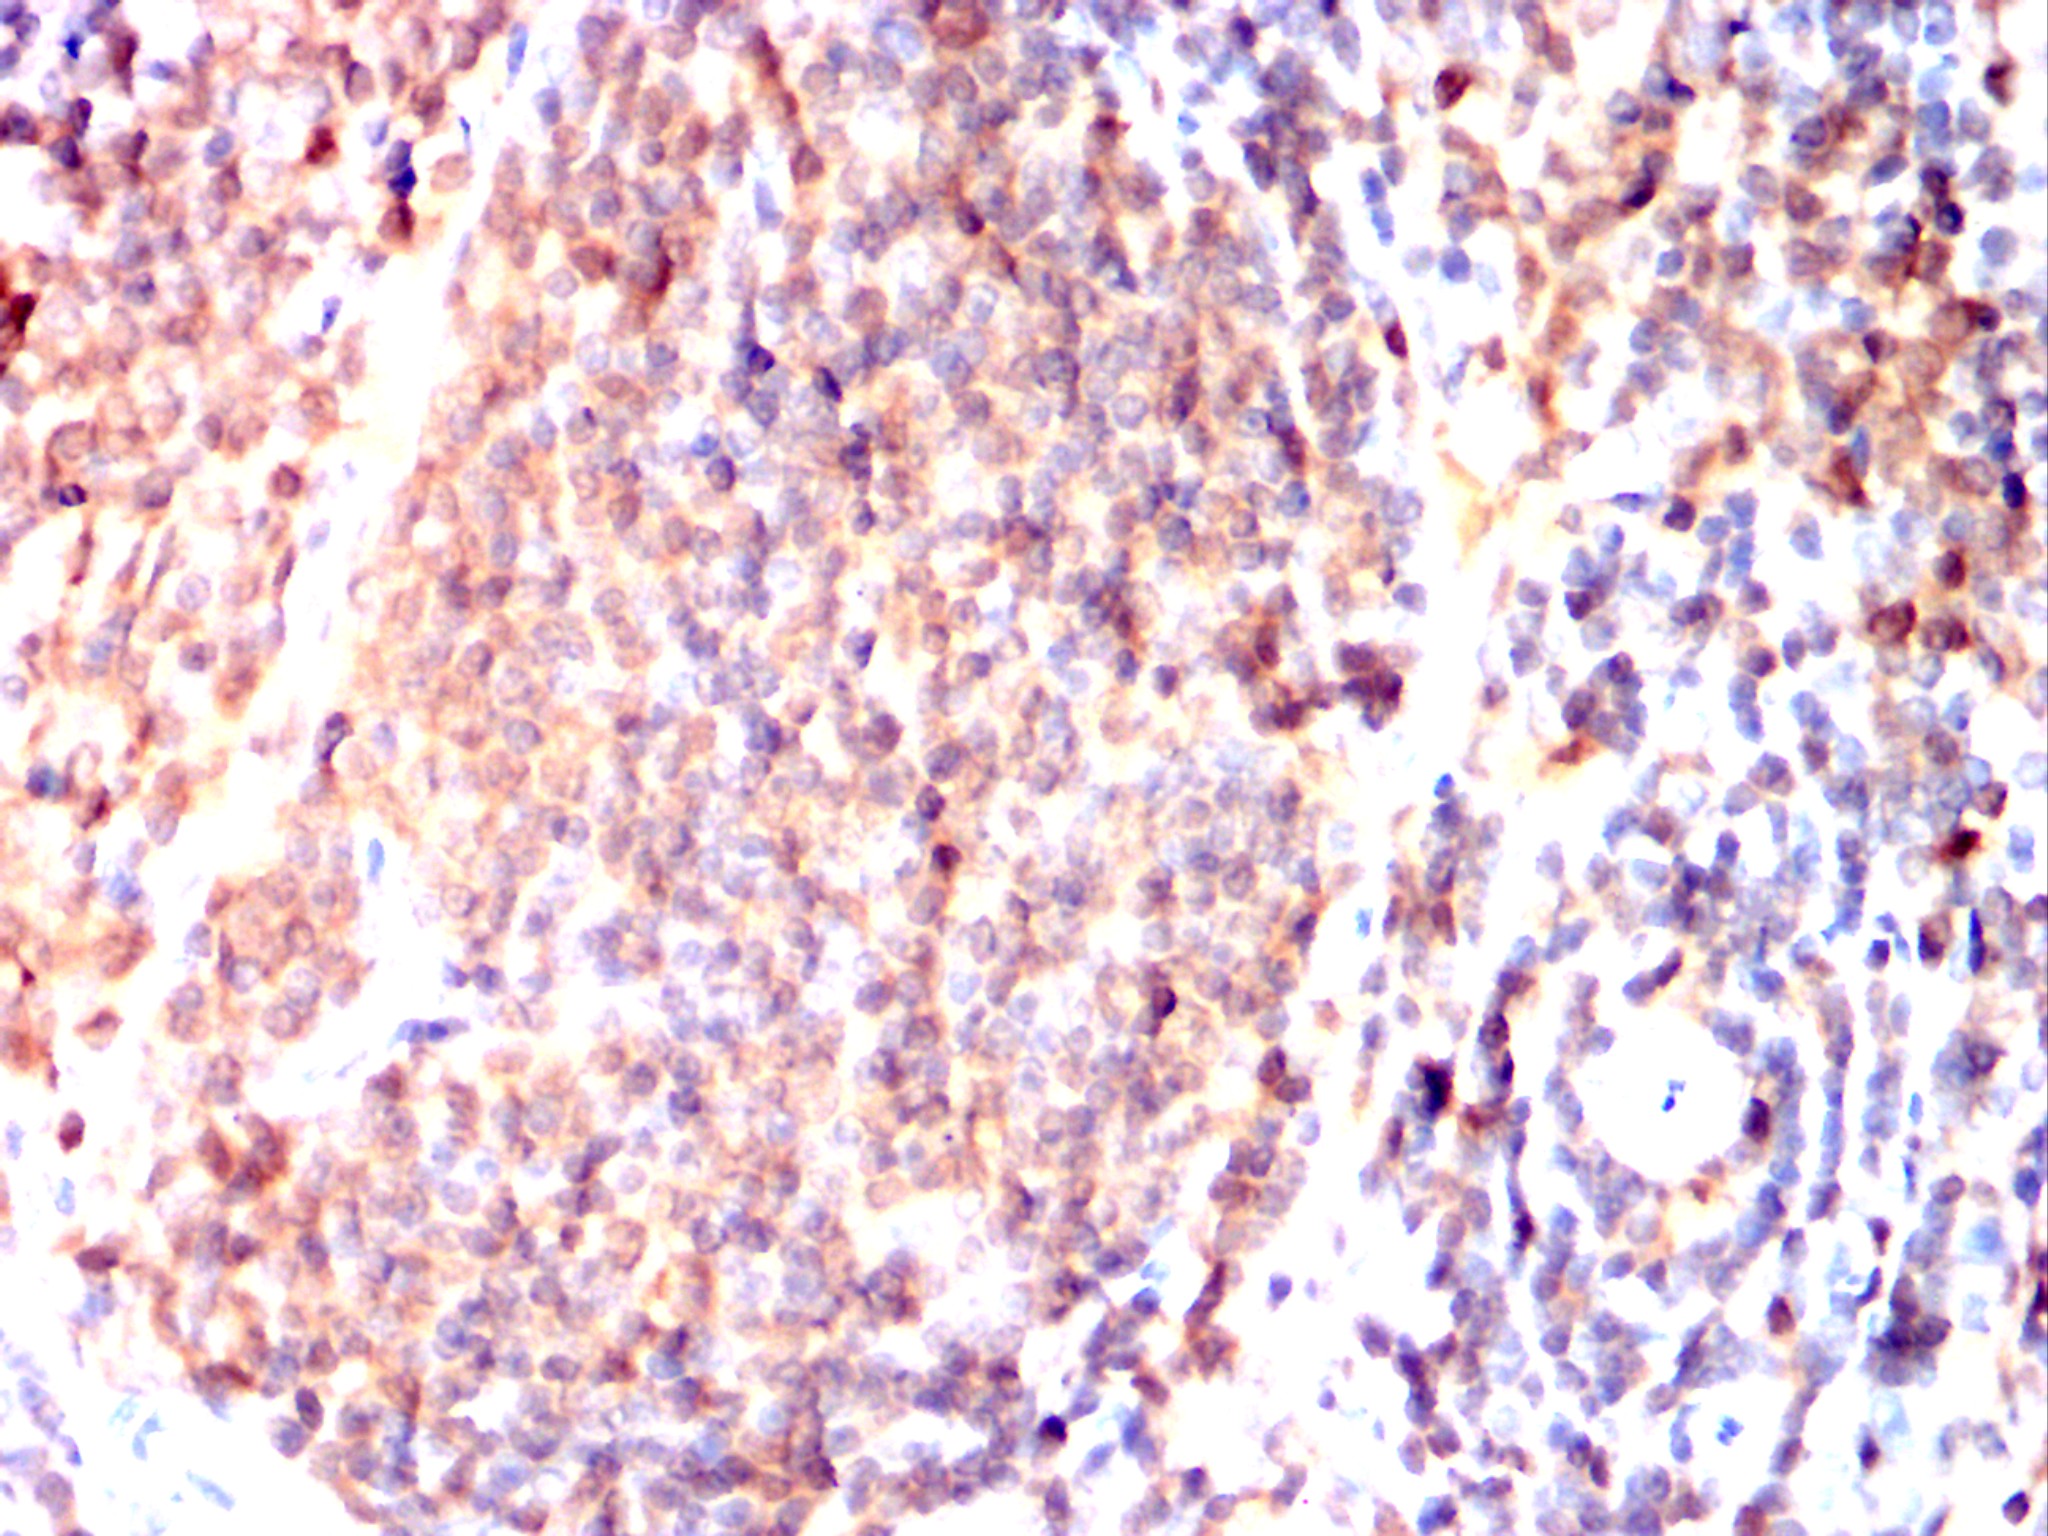

Immunohistochemical analysis of paraffin-embedded Mouse spleen using IRAK4 mouse mAb with DAB staining.

Immunohistochemical analysis of paraffin-embedded Rat spleen using IRAK4 mouse mAb with DAB staining.